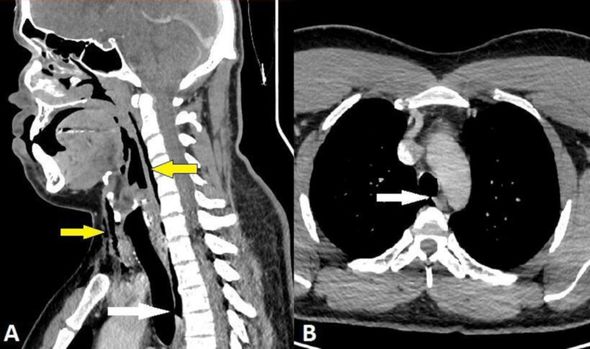

Boynun rentgenoqrafiyasından məlum olub ki, kişidə cərrahi amfizem var. Bu vəziyyətdə hava dərinin altındakı toxumanın ən dərin təbəqələri altına yığılır. Daha sonra kompüter tomoqrafiyası (KT) skaneri göstərib ki, yırtıq onun boynunun üçüncü və dördüncü fəqərələri arasındadır. Sinəsinin ağciyərləri arasındakı boşluqda da hava toplanıb.

Həkimlər belə nəticəyə gəliblər ki, yırtıq burunu sıxmaq və eyni zamanda ağzı bağlamaqla olan asqırma zamanı nəfəs borusunda təzyiqin sürətlə artması nəticəsində yaranıb.